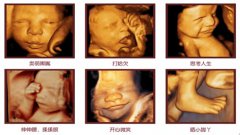

四维彩超是彩色的吗? 现在对很多孕妈妈来说,做四维彩超已成为常规产检流程,相比...[详情]

安琪儿专家解答:为什么要做四维彩超? 孕妈妈在孕期都会进行B超检查,随时监测宝...[详情]